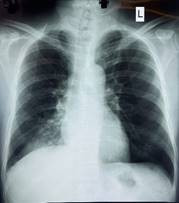

Hình: Viêm phổi tại phân thùy S6 phải - Ảnh BVCC

Bệnh nhân V.N.L (64 tuổi), trú tại xã Thới Lai, thành phố Cần Thơ, nhập viện trong tình trạng sức khỏe suy yếu do ho khan dai dẳng, thỉnh thoảng khạc đàm đục và sốt nhẹ kéo dài suốt nhiều tháng. Dù đã điều trị ngoại trú tại nhiều cơ sở y tế nhưng tình trạng bệnh không thuyên giảm, khiến chất lượng cuộc sống của bệnh nhân bị ảnh hưởng nghiêm trọng.

Qua thăm khám chuyên sâu và các kỹ thuật chẩn đoán hình ảnh, các bác sĩ Bệnh viện Lao và Bệnh Phổi Cần Thơ đã phát hiện dị vật mắc kẹt trong đường thở là nguyên nhân chính gây ra các triệu chứng trên. Ngay lập tức, ê-kíp can thiệp nội soi phế quản được kích hoạt khẩn cấp.